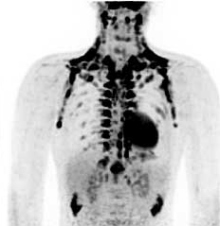

El estudio utilizó imágenes de PET con 18F-FDG para documentar la cantidad de grasa parda en niños, la cual, a diferencia de la grasa “blanca” o tejido adiposo común, libera energía en lugar de almacenarla. Los resultados fueron publicados en The Journal of Pediatrics.

En esta nueva investigación, los autores revisaron retrospectivamente los estudios PET realizados en 172 pacientes de 5 a 21 años en el Hospital de Niños de Boston. Detectaron grasa parda activa en el 44% de los casos, con una tasa semejante para niñas y niños. Los niños entre 13 y 15 años tuvieron el porcentaje más alto de grasa marrón y presentaron la más alta actividad metabólica de la misma. Pero además, el índice de masa corporal (IMC) se correlacionó inversamente con la actividad de grasa parda, lo que significa que los pacientes más delgados tuvieron la mayor actividad.

"Creemos que la posibilidad de evaluar de forma no invasiva la actividad de grasa parda en vivo mediante PET proporciona una mejor comprensión de su papel en la fisiología pediátrica, y quizás pueda aportar ideas para el tratamiento de la obesidad infantil", dijo el primer autor del trabajo, Laura Drubach, del programa de Medicina Nuclear e Imagen Molecular del Hospital de Niños. Por su parte, Cypess dijo que el objetivo sería la búsqueda de formas no farmacológicas para aumentar la actividad de la grasa parda, tal vez mediante el establecimiento de una temperatura interior más fría en los hogares donde habitan los niños obesos. Ciertos alimentos también podrían desempeñar un papel en el aumento de los niveles de grasa parda; de lo contrario, el desarrollo de nuevos fármacos podría ser la respuesta, añadió.

Es bien conocido que la presencia de grasa parda, debido a su elevada actividad metabólica, suele dificultar la interpretación de los estudios PET con FDG.